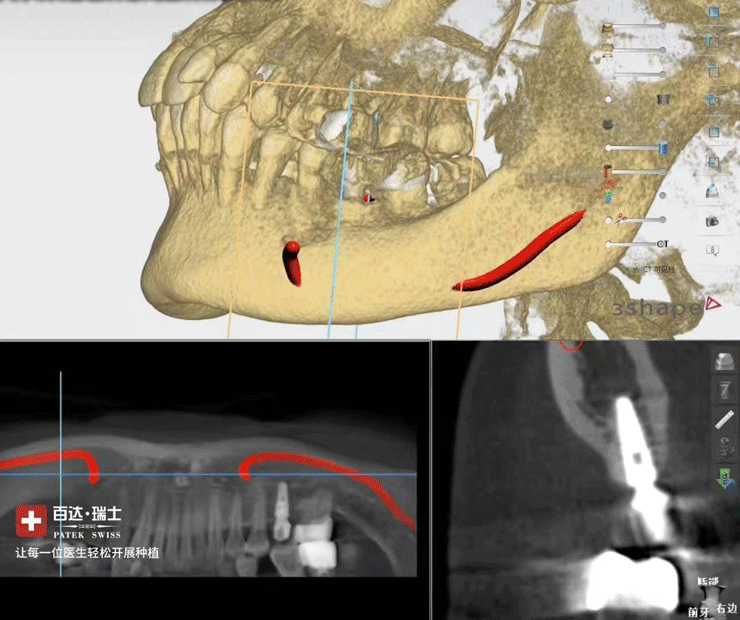

靖佳齿科黑科技项目—百达*瑞士,在技术上将术前虚拟设计种植方案在手术中精准植入顾客口内,极大提升临床种植的精准度,在开展方式上百达*瑞士极大的降低了医生成本,让每一位医生都能轻松开展种植!靖佳齿科一直不断致力于创新和引进新技术,为合作伙伴创造价值,携手靖佳,共创未来!